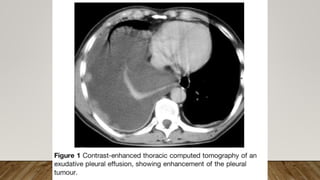

This document discusses pleural diseases. It was written by Eman Abdallah Aboelenein, who has an MSc and works as an assistant lecturer of hemato-oncology and bone marrow transplantation at the hematology unit of the internal medicine department of the faculty of medicine at Tanta University Hospitals. The author thanks the reader for their time and attention.